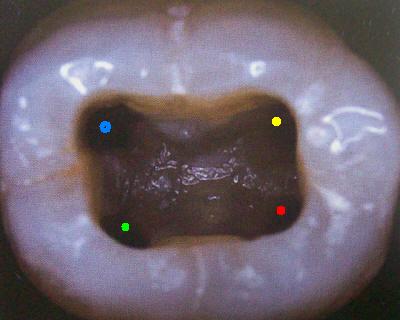

Cuarto conducto en molares inferiores (Color amarillo) |

Primer Molar Inferior Esta pieza dentaria es la más voluminosa de la arcada. Posee por general dos raíces bien definidas una mesial y otra distal, ambas aplanadas en sentido mesiodistal. La raíz mesial presenta una curvatura acentuada, mientras que la distal puede ser algo curva o recta. Cuando tiene tres conductos el mas amplio es el distal con una sección oval y su curvatura es suave o recta. Si presenta cuatro conductos la raíz distal contendrá dos de ellos y son de diámetro más pequeño y en caso de presentar dos conductos, ambos son amplios. Segundo Molar Inferior Es de menores proporciones que el primer molar y sus raíces en general son dos y diferenciadas como en el primer molar ,así como también pueden presentarse fusionadas parcial o totalmente. |